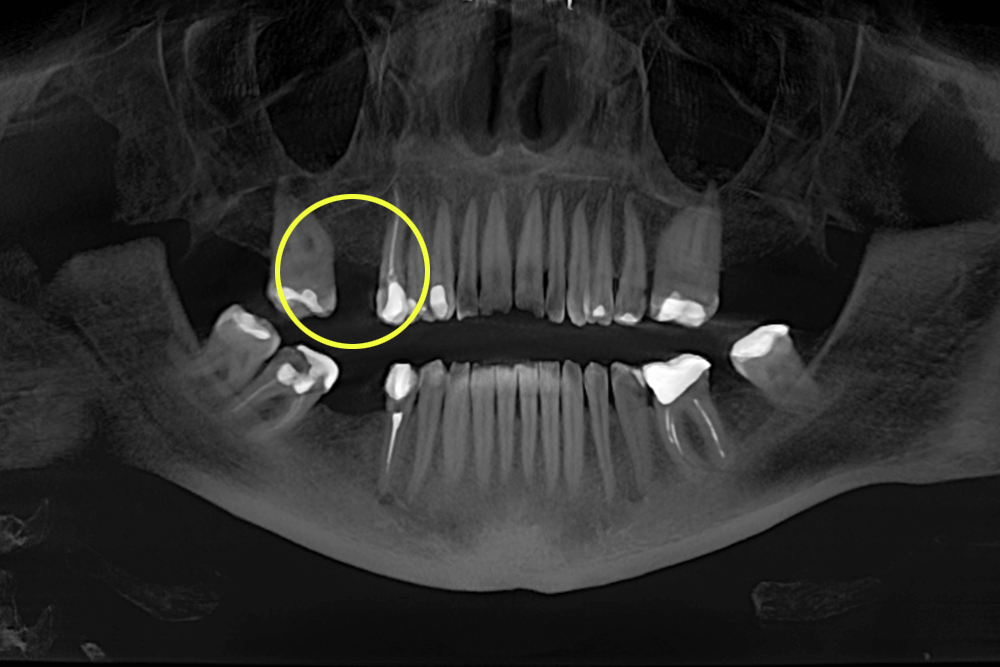

Во время консультации врач увидел на КТ-снимке отсутствие зуба 1.6 (на верхней челюсти справа), зуба 3.7 (на нижней челюсти слева), на место которого сместился зуб 3.8 (вот почему не стоит спешить удалять "восьмерки", если нет прямых показаний) и зуба 4.6 (на нижней челюсти справа), на место которого мигрировал зуб 4.7.